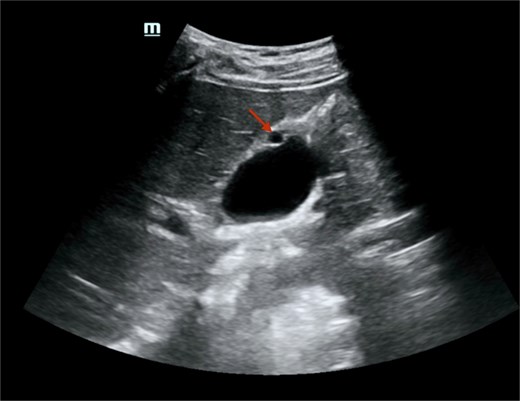

Imaging findings: A non-contrast computed tomography (CT) scan of the abdomen revealed a mild left hydroureteronephrosis caused by a distal obstructive ureteric stone. Incidentally, the scan showed a focal thickening of the gallbladder fundus wall (Fig. 1). Correlation with abdominal ultrasound identified a well-defined 7 mm cystic lesion within the gallbladder wall (Fig. 2). The liver, spleen, and other abdominal organs appeared normal on CT.

Abdominal ultrasound showed a well-defined, round, anechoic lesion within the gallbladder wall, measuring about 7 mm, likely representing a foregut cyst of the gallbladder. There was no peri-cholecystic edema, obvious shadowing stones, or increased wall thickness.